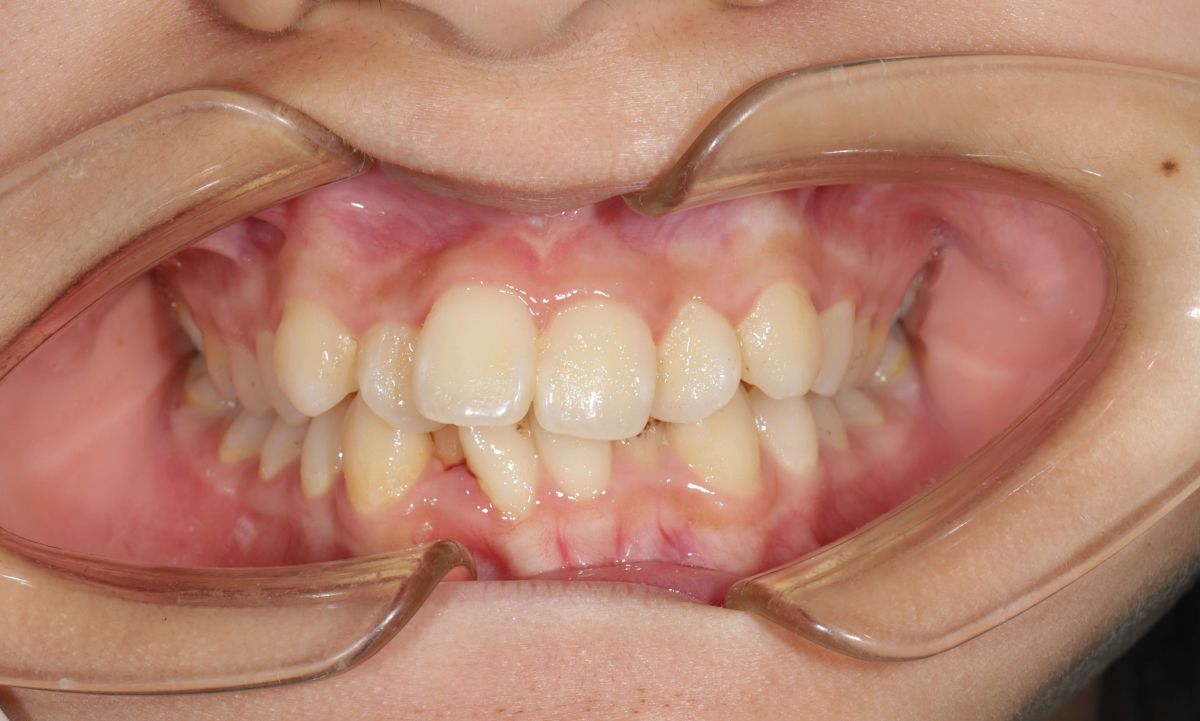

Tình trạng trước niềng răng

Sau khi thăm khám tại Nha khoa Hanseoul, bác sĩ ghi nhận các vấn đề:- Răng lệch lạc, chen chúc nghiêm trọng cả hai hàm

- Không đủ khoảng sắp xếp răng

- Khớp cắn sai (cắn chìa – cắn sâu)

- Ảnh hưởng thẩm mỹ khuôn mặt và chức năng ăn nhai